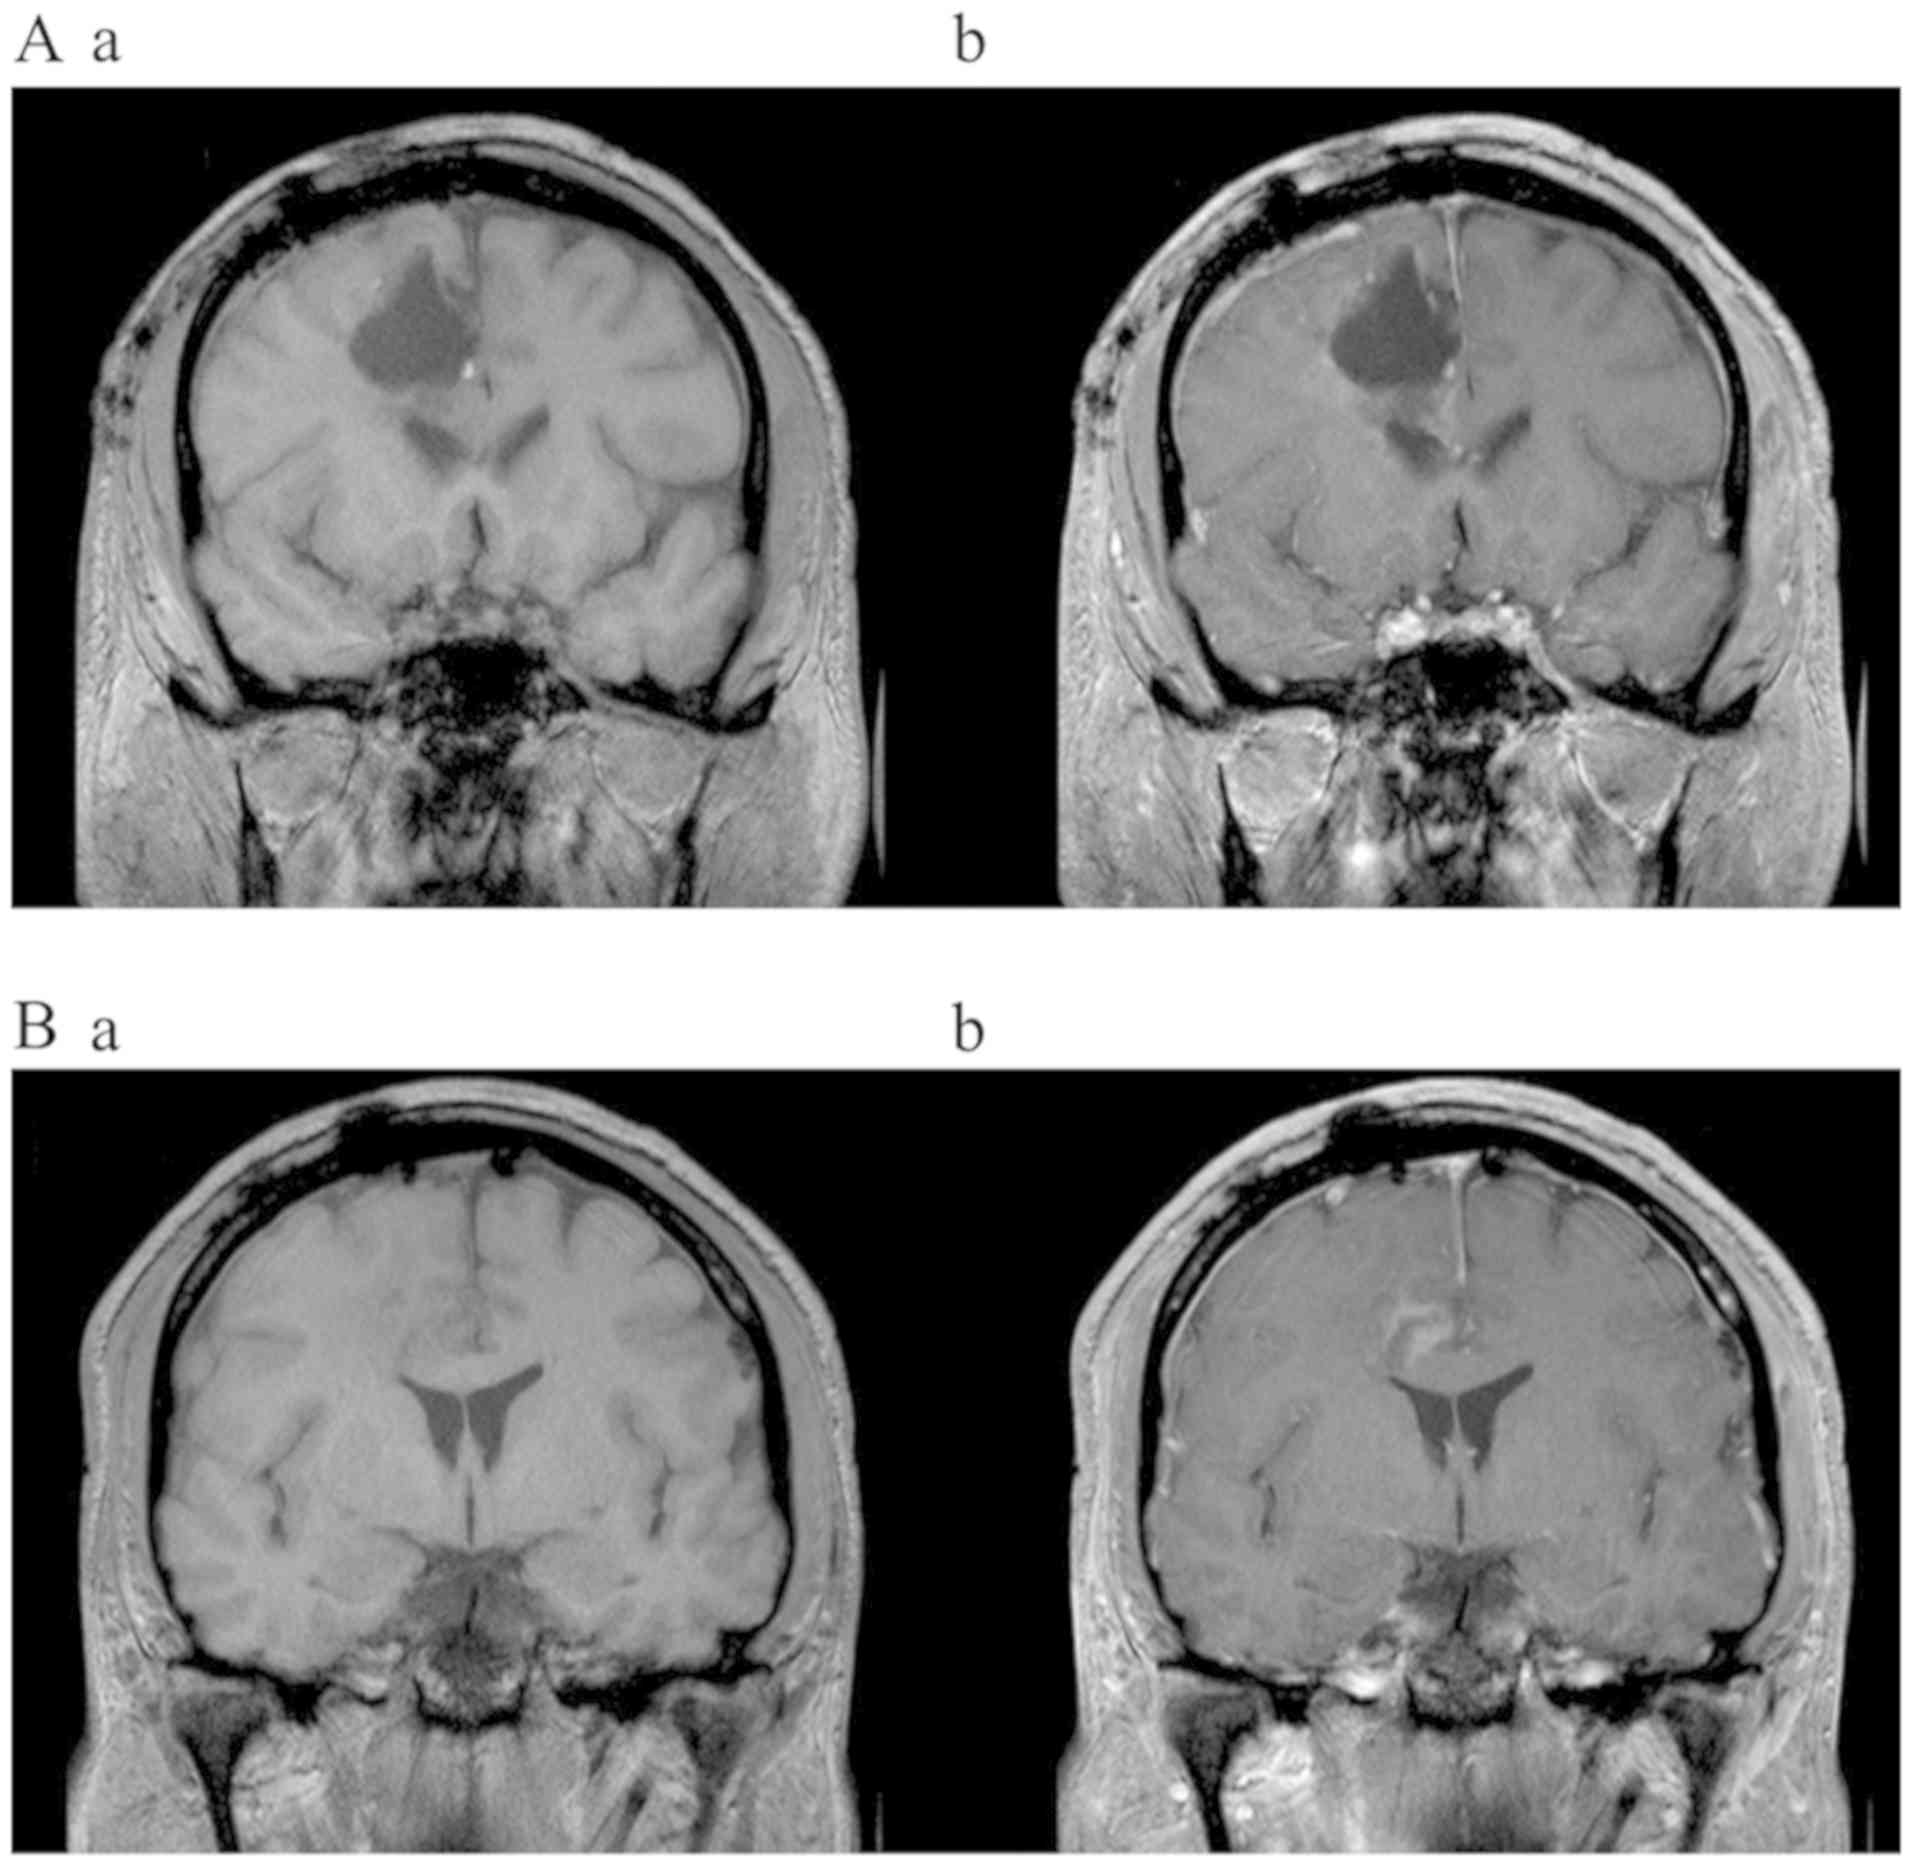

Patient two (female, 46 years, KPS 90%) displayed a right-sided hemiparesis. Her MRI revealed a left parietal lesion infiltrating the post-central gyrus. After STR contrast enhancement was still discernible at the resection margins 24 h after surgery (Fig. 2A). Histopathology confirmed GBM (methylated MGMT promoter, IDH1/2 WT, sustained nuclear expression of ATRX). Postoperative irradiation up to 61.2 Gy administered with concomitant daily TMZ (75 mg/m2) was well tolerated. Six cycles of adjuvant TMZ therapy were administered concomitantly with TTFields, which were applied for 14 months at compliance rate of above 90%. Four months after initiating TMZ + TTFields, MRI revealed a CR of the residual tumor (Fig. 2B). After a follow-up period of 16 months, MRI did not show any signs of tumor recurrence.

Figure 2.

Axial T1-weighted MRI [native (Aa/Ab)] and contrast enhanced (Ba/Bb) images of patient two (female; 46 years old). (A) Incomplete tumor resection is indicated at 24 h post-surgery. (B) Axial T1-weighted MRI exhibiting complete response 6 months after surgery and 4 months after the initiation of TTFields treatment. TTFields, Tumor Treating Fields.